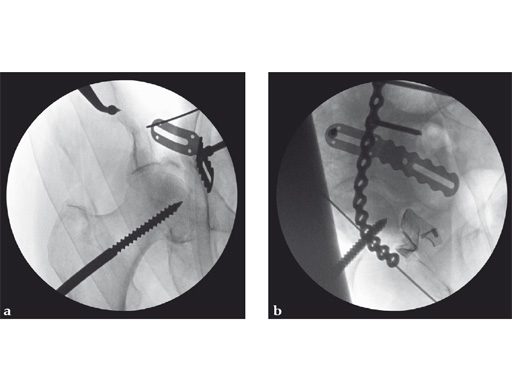

Fig 2ab Intraoperative AP hip and iliac oblique image intensifier images of a portion of the reduction sequence utilizing distal/lateral traction through a Schanz screw, ball spike (picador) with disc and asymmetrical reduction clamp with disc. The remaining area of incompletely reduced articular surface was a free, thin osteochondral fragment retrieved through the anterior column fracture. It was reoriented and trapped between the lateral articular surface, displaced anterior column, and femoral head. Despite multiple attempts this position could not be further improved. Cancellous autologous bone graft was used to buttress this area through a small internal iliac fossa cortical window.